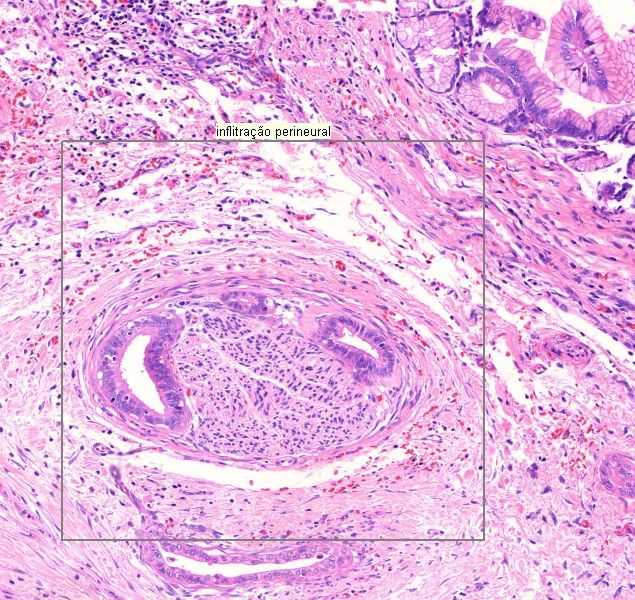

1. Adenocarcinoma ductal (4210H)

1. Infiltração perineural

2. Adenocarcinoma de vesícula (A524)

1. Fibrose

1. Reação desmoplásica

2. Glândulas com padrão infiltrativo

1. Alteração arquitetural

1. Pleomorfismo

1. Núcleos de um mesmo tipo celular tem formas diferentes